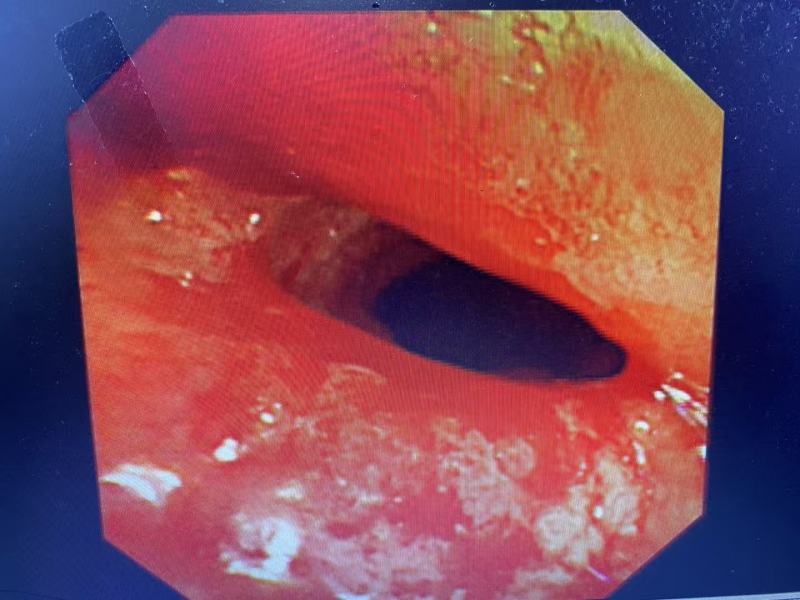

看着黄先生痛苦不已,家属心急如焚,打听到自治区南溪山医院院呼吸与危重症医学科二病区有神奇的呼吸介入手术可缓解呼吸困难,遂于春节期间紧急转至该病区。屈东明博士查看资料后迅速组织完善术前检查,呼吸介入团队联合麻醉科、内镜中心联合制定个性化方案。在全麻下行沙漏型硅酮支架植入术,术中发现患者情况更为严重,因肿瘤侵犯气管扭曲,鞘管无法通过最狭窄部位,同时支架推送器也无法通过鞘管。呼吸介入团队经过商量后迅速调整手术方案,终于成功植入气道支架,患者从“命悬一线”到自由呼吸!

屈东明博士介绍:硬质气管镜下置入支架,通俗来讲,就是在不开刀的情况把狭窄的气管扩张到趋于正常气道的大小。气管支架置入术是一项高风险、高难度的医疗技术,尤其是恶性肿瘤压迫气道狭窄的患者。动作轻了、慢了,支架无法通过狭窄或者卡在了狭窄部位,有可能造成患者窒息,手术失败。动作用力过猛,又很有可能造成气道损伤加重,术后并发症增多。